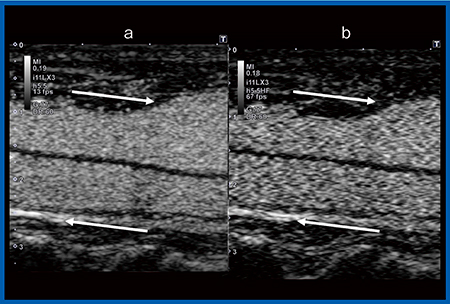

超音波パルスの送受信で画像化を行う超音波診断装置では,体内の速い変化をとらえるためにはフレームレートを上げる必要がある。そのために開発されたのが,“High Frame Rate CHI(HFR-CHI)”である。図1は,総頸動脈と内頸静脈を同一画面に表示した造影超音波画像だが,Original CHI(a)ではMI(Mechanical Index)を経時的に低下させ造影剤の反応を低減させても血流の方向ははっきりしないが,HFR-CHI(b)では流れている方向が確認でき,血管壁に接する部分の血流の動きが少ないことまで視認が可能になった。

図1 総頸動脈と内頸静脈の造影超音波

a:Original CHI b:HFR-CHI